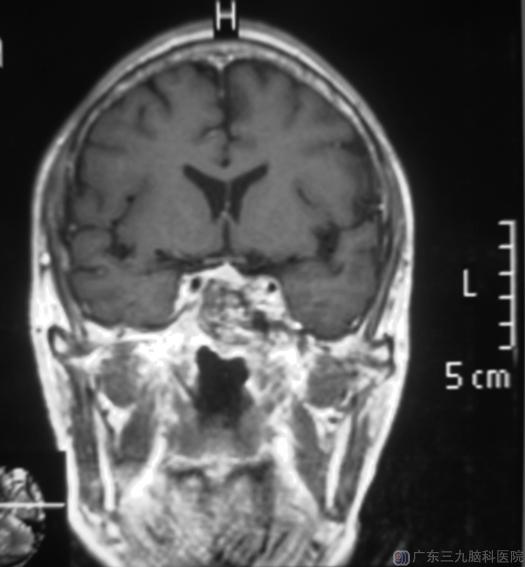

综合神经外科鲁明主任主刀,在全麻下行经鼻蝶鞍区占位切除术,显微镜下见蝶窦内异常肿瘤组织,质软、黄色油脂状,吸出部分组织后,见鞍底破坏,切开肿瘤包膜,刮匙全部刮除肿瘤,手术顺利。术后老胡诉左眼视力明显好转。术后病理结果:胆脂瘤。